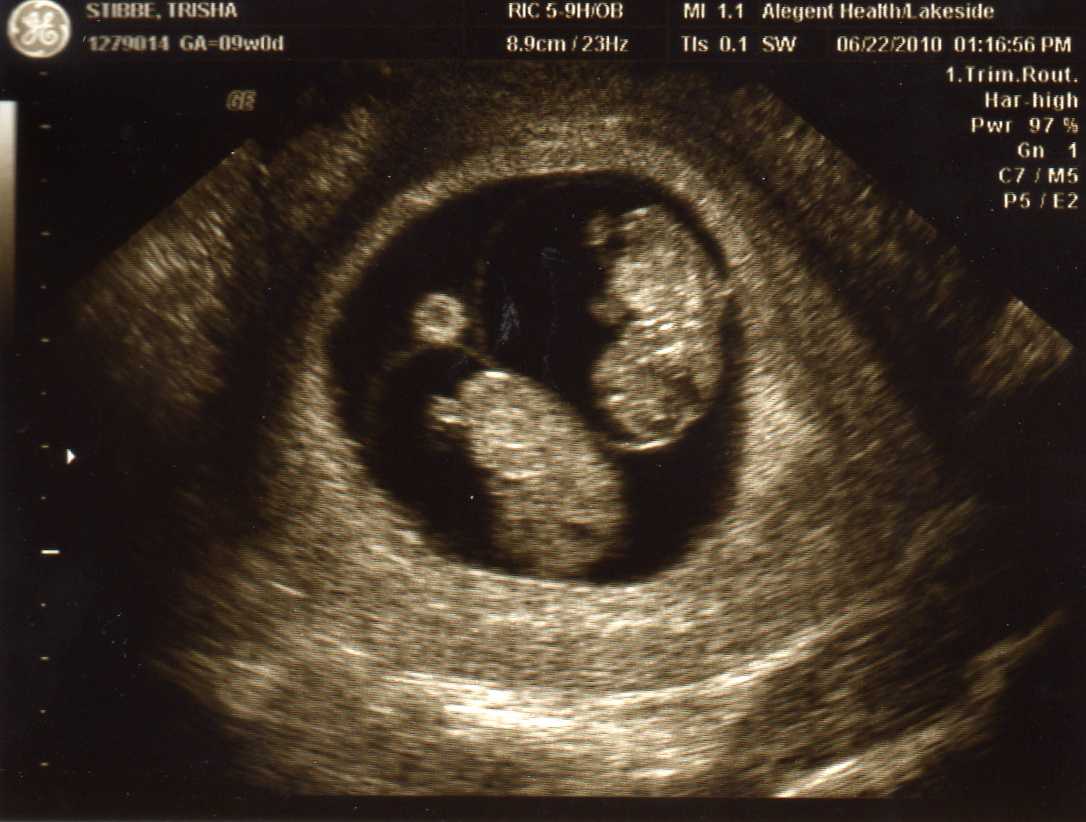

By now most of you have heard… Adam and I are expecting! Not just 1… but 2!!! Right after our appointment, I journaled the following… the babies’ first picture is at the bottom: )

We had our ultrasound first… right away you could see a little “peanut.” That made it very real. Then, our ultrasound tech began to move around the wand, and said, “Look at the baby! So cute. Look…at…the…babies!!!” I about fell off the table. Adam’s reaction- “I thought that’s what it looked like.” My reaction- “What?!”

Sure enough, two little babies. Measuring perfectly, great heartbeats, and the ultrasound showed that the babies will probably be identical, although we’ll know for sure in a few more weeks.